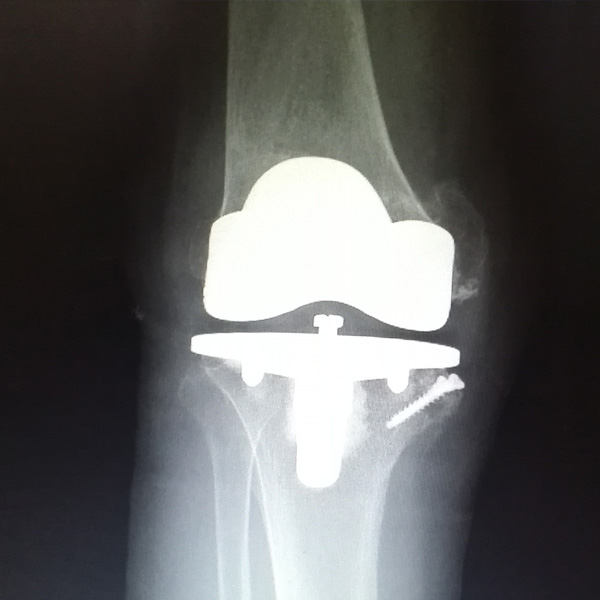

膝關(guān)節(jié)內(nèi)翻

患者劉某某,女66歲,左側(cè)膝關(guān)節(jié)嚴(yán)重內(nèi)翻(俗稱的“羅圈腿”),疼痛到不能生活自理。經(jīng)平臺推薦到哈爾濱醫(yī)科大學(xué)附屬第二醫(yī)院骨關(guān)節(jié)科就診,......